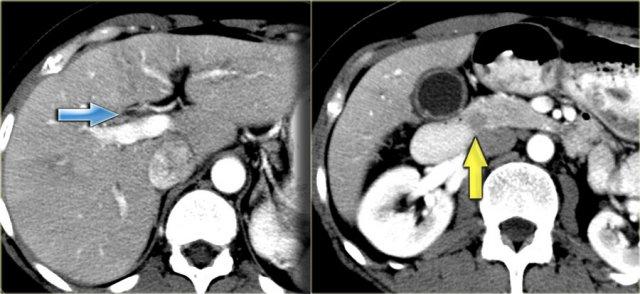

Hình ảnh CT

Trên CT, gan trông khá bình thường.

Tuy nhiên, nếu quan sát ống mật chủ ở vùng đầu tụy, bạn sẽ nhận thấy vùng tỷ trọng mô mềm.

Chẩn đoán phân biệt bao gồm sỏi kẹt hoặc ung thư đường mật, nhưng vì bệnh nhân này không có tắc nghẽn, tình trạng này được cho là do thành ống mật dày lên.

Thành túi mật cũng dày lên.